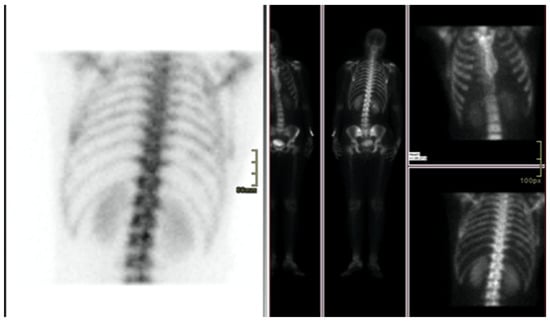

We report the case of a 47-year-old pre-menopausal Caucasian woman who presented to the Policlinico Umberto I hospital in Rome, with a 6-month history of subjective dizziness, oscillopsia, instability, imbalance, blurred vision, and photophobia, accompanied by severe vomiting, which resulted in severe weight loss (16 kg over 7 months) (Table 1). The medical history was significant for only hypothyroidism and her family history was positive for a sister with breast cancer. Clinical examination of our patient revealed marked fluctuations without prevalence to the side during Romberg and Fukuda tests, both with open and closed eyes. In video-oculoscopy (Supplementary Materials Video S1), the assessment of extraocular motility demonstrated isolated and intermittent episodes of low-amplitude, high-frequency horizontal saccades occurring without an intersaccadic interval, consistent with the clinical presentation of ocular flutter []. A comprehensive evaluation was performed, including contrast-enhanced brain Magnetic Resonance Imaging (MRI) (Figure 1), brain Computed Tomography (CT) scan (Figure 2), ophthalmological assessment, viral serology, autoimmune panel, complete blood count, and assessments of thyroid, renal, coagulation, hepatic function, vitamin D and B12 levels; all results were within normal limits. Paraneoplastic syndrome (ENS) sometimes precedes the diagnosis of cancer, necessitating a screening to detect an unidentified tumor. After excluding all other potential causes of the neurological symptomatology, a paraneoplastic origin was considered. Paraneoplastic autoantibody panels (anti-Ri, anti-Yo, anti-Hu, anti-CV2.1, anti-Amphiphysin, and anti-Ma2/Ta) resulted positive for anti-Ri onconeural antibodies with a value of 1:126 (51–256 strong positivity). A whole-body CT scan revealed multiple solid non-calcific nodules (at least 4 in the right breast QQEE), the largest measuring 13 × 9 mm, and right axillary lymphadenopathy measuring 24 mm (Figure 3). Mammography showed at least three nodular opacities with an irregular shape in the external superior quadrant of the right breast. The biggest ones were 13 mm (with intranodular microcalcifications) and 12 mm (BIRADS 5) (Figure 4). The breast ultrasound confirmed three solid irregular hypoechoic nodules measuring 11 mm, 9 mm, and 12 mm, as well as some right axillary lymphadenopathy, the largest measured 25 mm (Figure 5). Histological examination of an ultrasound-guided biopsy revealed invasive carcinoma “no special type” (NST) according to the 2019 World Health Organization (WHO) classification, with a grade 2 histology (G2) with occasional outbreaks of ductal carcinoma and axillary lymph node metastasis. Additionally, a bone scan revealed no evidence of the disease’s metastatic localization (Figure 6). A multidisciplinary team decided to proceed with a right mastectomy and a right axillary dissection. The final histopathological report showed an invasive multifocal NST grade 2 carcinoma, positive for ER (98%), PR (80%), Ki67 (32%) and negative for HER2 (Luminal B HER2 negative). The resection margins were free of neoplastic infiltration. Two of the 14 lymph nodes were positive for invasive carcinoma. The final staging was G2 pTle pNla (2/14) MO, stage IIA. The patient received hormone therapy (Exemestane 25 mg daily and Decapeptyl 3.75 mg daily) due to high hormone receptor expression. Surgical treatment of the primary tumor did not improve neurological symptoms, prompting the patient to undergo intravenous steroid therapy; however, this also did not lead to any clinical improvement. The patient was evaluated at 2, 6, 12 and 24 months with clinical, radiological and serological examinations. On vestibular examination 2 months post-surgery, subjective dizziness and instability persisted. On video-oculoscopy, the patient presented ocular flutter with intermittent horizontal saccades especially in the lateral gaze. Total body CT scan (Figure 7) and breast ultrasound (Figure 8) at 2 months were negative for neoplastic recurrence or metastases. Serology for anti-Ri antibodies remained positive. Six months after surgery, the patient, who had been on Prednisone 50 mg/day, was admitted to the neurology department of another hospital. Patient reported an improvement in headache and a reduction in the frequency of emesis, but no improvement of the ocular and vestibular symptoms. The neurological examination documented oculovestibular syndrome with ocular flutter that was not inhibited by fixation, forcing the patient to keep her eyes closed, ataxia, head and trunk tremor, hypomimic facies, hypertonia in the right upper limb with difficulty in movements of the right hand, difficulty getting up from the chair without support, instability in open and closed eyed Romberg test, moon facies due to iatrogenic Cushing’s, slow, diprosodic and hypophonic speech. During admission, an MRI of the brain and brainstem was performed, which showed a slight enlargement of the peri-brain spaces in the frontal area and of the peri-brain spaces in the cerebellar area, possibly indicative of initial atrophy. Blood tests confirmed the presence of anti-Ri antibodies. Considering the immune-mediated genesis of the paraneoplastic syndrome, the patient underwent five sessions of plasmapheresis followed by a course of intravenous immunoglobulin (0.4 g/kg/day) with a slight and temporary clinical improvement. Due to the presence of a mild right rigid-kinetic hemi-syndromes with associated hypomimia and hypophonia, a genetic study for Parkinson’s disease was conducted and L-DOPA therapy was prescribed, which was then discontinued as the patient reported worsening symptoms. The patient underwent brain SPECT with receptor tracer to evaluate the presynaptic dopaminergic system the basal ganglia, which showed no impairment of the nigrostriatal presynaptic dopaminergic system. Due to the lack of response to chronic steroid therapy and the development of clinical signs of iatrogenic Cushing’s, following endocrinological consultation, the dosage of Prednisone was progressively reduced and then replaced by Cortone Acetate. Bone mineral density was normal. After one month, the patient was transferred to a rehabilitation center to undergo neuromotor and vestibular rehabilitation until the patient was transferred back to the prior neurology department due to a clinical worsening, in particular of the eye complaints. The patient was unable to perform more than a few steps without support, showed multidirectional fluctuations on the Romberg test with trunk instability. At eye opening there was persistence of the ocular flutter, with mydriatic pupils (left > right) and a cloudy but present response to direct light stimulus. The other cranial nerves were intact. Thermal tactile and pain sensitivity were preserved. Osteotendinous reflexes were brisk and symmetrical in the upper limbs and hypotensive in the lower limbs. Coordination tests (index-nose, index-index, finger-tapping), revealed mild motor impairment on the right side with kinetic and postural tremor and fine tremors in the upper limbs. During hospitalization, the patient underwent a new course of plasmapheresis (four sessions in 8 days) combined with intravenous immunoglobulins (0.4 g/kg/day for 4 days) with slight clinical benefit. Due to the need for chronic immunosuppressive treatment, oral therapy with Azathioprine at an initial dosage of 25 mg/day, later increased to 50 mg, was administered. A contrast-enhanced MRI of the brain and cervical spine was performed, which showed essentially unchanged findings compared to the previous check-up, including a modest enlargement of the peri-brain spaces in the frontal area and peri-foliar spaces in the cerebellum, expressing initial signs of atrophy. Slight clinical improvement was documented during hospitalization, particularly in head tremor and ocular flutter, allowing the patient to fixate, despite the persistence of pathological eye movements. Gait was improved, although the patient remained ataxic. In view of this progress, the patient was again transferred to the neuromotor rehabilitation center for one month at the 12 months follow-up visit, the patient reported a worsening of the oculovestibular syndrome with inexhaustible flutter preventing fixation, worsening of rigidity in the right upper limb and occasional dysphagia. The neurological examination showed dystonic flexion in the right upper limb and plastic hypertonia in the upper limbs bilaterally (right > left), but no hypertonia in the lower limbs. Independent ambulation was not possible. The patient had an intravenous infusion of cyclophosphamide, which brought only slight and transient improvements in symptoms. After 24 months from the surgery, the patient was re-evaluated in our hospital, and a vestibular examination via oculoscopy confirmed the presence of the flutter with horizontal saccades, which were slightly reduced compared to the first assessment in 2022. Vestibulospinal tests revealed a severe postural deficit, with ataxic walking and right upper limb rigidity.

Figure 6. Bone scan not revealed evidence of the disease’s metastatic localization.